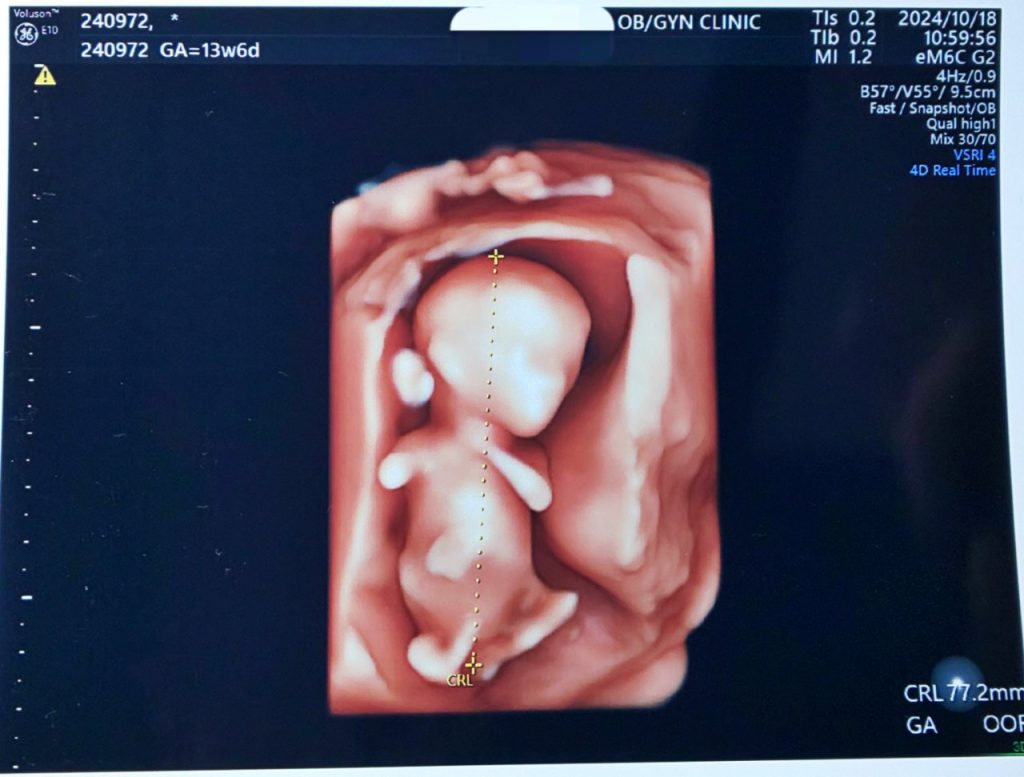

10/18 13w6d 全長77.2mm

前回29.2mm→今回77.2mmと48mmサイズアップ!前回のポケモンのコクーンから人間の形になっていました。モニターに映し出されている間、お子は腕を曲げたり伸ばしたり、口をパクパクさせたり、おしゃぶり(!)したり、足をもぞもぞさせたりしていて可愛かった~!股間の突起はへその緒のため性別不明。次の健診でわかるかも?